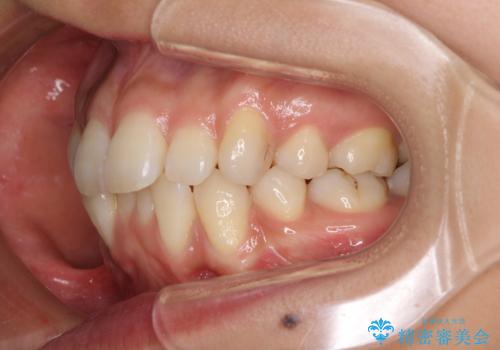

- 以前の矯正治療の後戻りにより、上下の前歯がでこぼこになってしまったことを気にして来院された患者様です。

口元がこれ以上突出することなく前歯の叢生が改善できるよう、歯と歯の間を削ってスペースを獲得し、インビザラインを用いて整えていくこととしました。

目安の装着時間である1日22時間をしっかりと実践してくださり、半年強という短期間で治療を終えることができました。